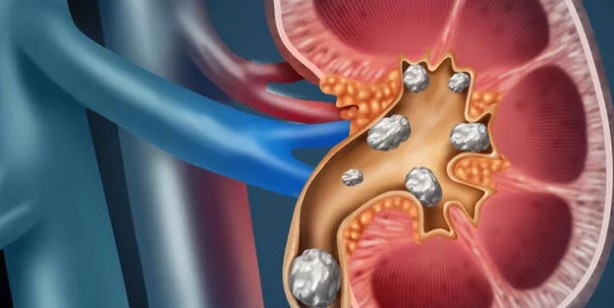

Böbrek taşı oluşumuna yatkın olanlar ayrıca oksalat içeren gıdaların (örneğin pancar, ıspanak ve kakaoda bulunur) ve ürik asit taşları durumunda pürin içeren gıdaların (örneğin hamsi, sardalya, kuşkonmaz vb.) sınırlandırılması gerekir. İşte böbrek sağlığını korumada etkili olduğu tespit edilen yaygın olarak kullanılan 10 besin.